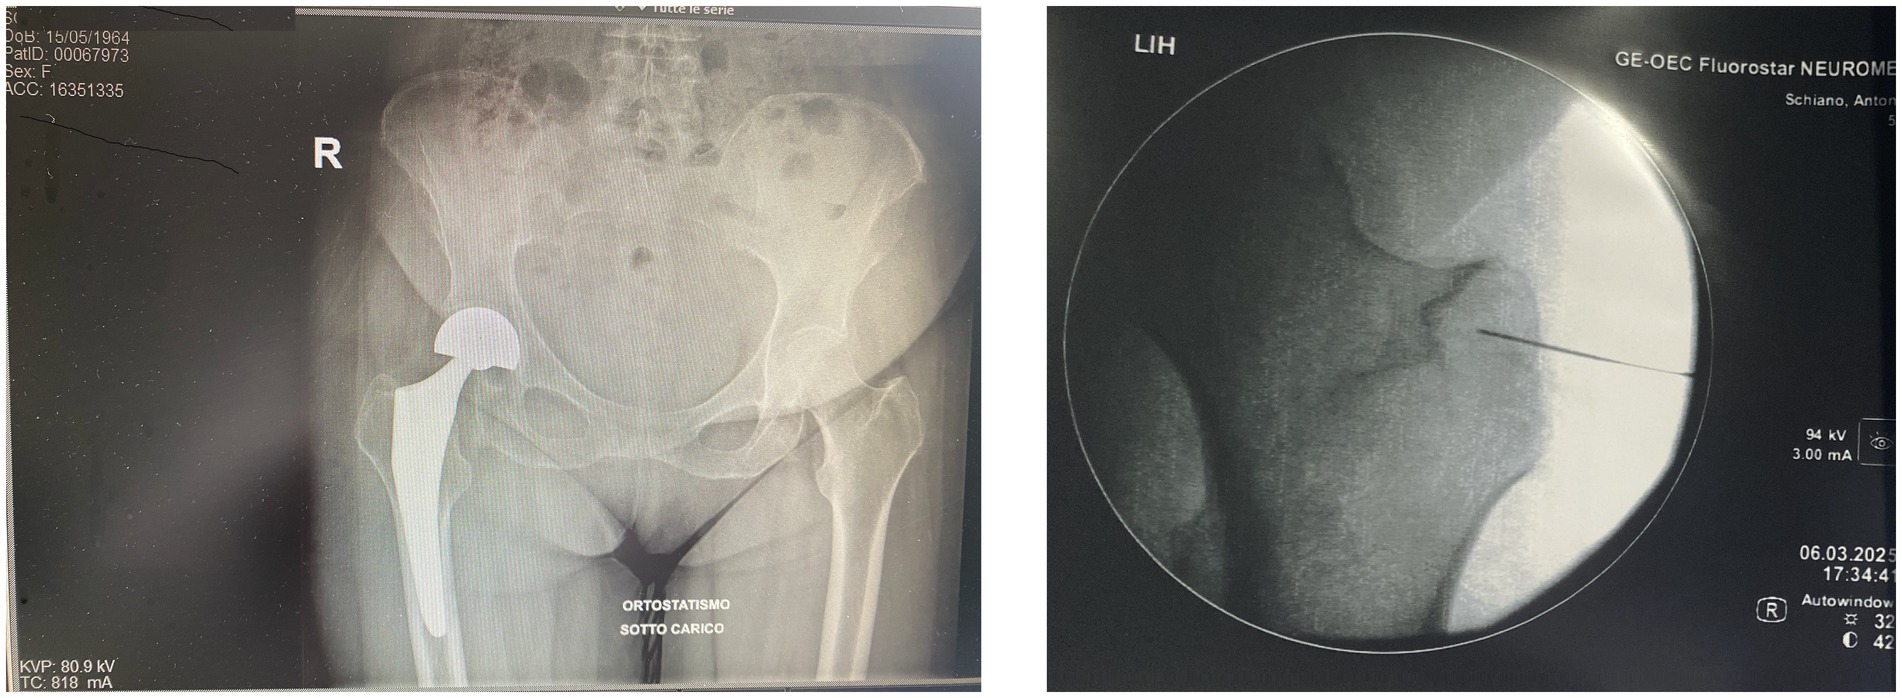

Postoperative imaging, including standard hip radiographs, confirmed proper alignment of the prosthesis with no evidence of loosening, dislocation, or other mechanical complications. Therefore, surgical revision was not indicated. The overall clinical picture was consistent with a manifestation of Spasticity-Plus Syndrome. Two months after surgery, treatment was initiated with nabiximols (Sativex®), an oromucosal spray formulation of THC: CBD approved for the treatment of spasticity in MS (6, 7). However, the patient reported minimal benefit. Although nabiximols (Sativex®) are considered effective in cannabinoid-responsive symptoms and have contributed to the formulation of the Spasticity-Plus Syndrome (SPS) concept, the patient experienced only minimal improvement (7, 8). This may reflect the predominance of peripheral nociceptive inputs and segmental sensitization mechanisms less amenable to central cannabinoid modulation. Additionally, individual variability in endocannabinoid system responsiveness could play a role. These findings reinforce the hypothesis that SPS includes subtypes with differing pathophysiological profiles, some of which may benefit more from peripheral neuromodulation (7) than from systemic pharmacotherapy (1–8). Before considering neuromodulation, the patient was treated with a wide range of pharmacologic therapies. These included paracetamol and NSAIDs, pregabalin up to 300 mg/day, duloxetine 60 mg/day, benzodiazepines (e.g., diazepam), transdermal buprenorphine (up to 25 mcg/h), and transdermal fentanyl (up to 25 mcg/h) (9). For breakthrough pain, fentanyl lollipops were also used. Although MS is a highly prevalent autoimmune disorder. Opioid peptides and their receptors are intimately involved in regulating various aspects of immune function, nociceptive processing, and affective states. Dysregulation of the opioid system may be an important mechanism to help explain the pathophysiology of MS, as well as the pathological pain and disordered mood commonly observed in this disease. Therefore, it is of interest to further investigate and consider the opioid system as a potentially at- tractive therapeutic target for MS and its symptoms (9).

Figure 1. Composite image. The anteroposterior radiograph (left) shows our patient’s right total hip arthroplasty in a standing, weight-bearing position, with proper alignment of prosthetic components and no radiographic signs of loosening or mechanical complications. The intraoperative fluoroscopic image (right), adapted from our interventional protocol, shows precise placement of pulsed radiofrequency (PRF) electrodes near the trochanteric branches of the femoral nerve. The procedure was followed by targeted PRF treatment of the articular branches of the femoral and obturator nerves under fluoroscopic guidance. PRF is used to modulate peripheral nociceptive pathways without causing structural nerve injury, representing a promising therapeutic option in patients with chronic post-arthroplasty hip pain. Reference: Chye et al. (5).